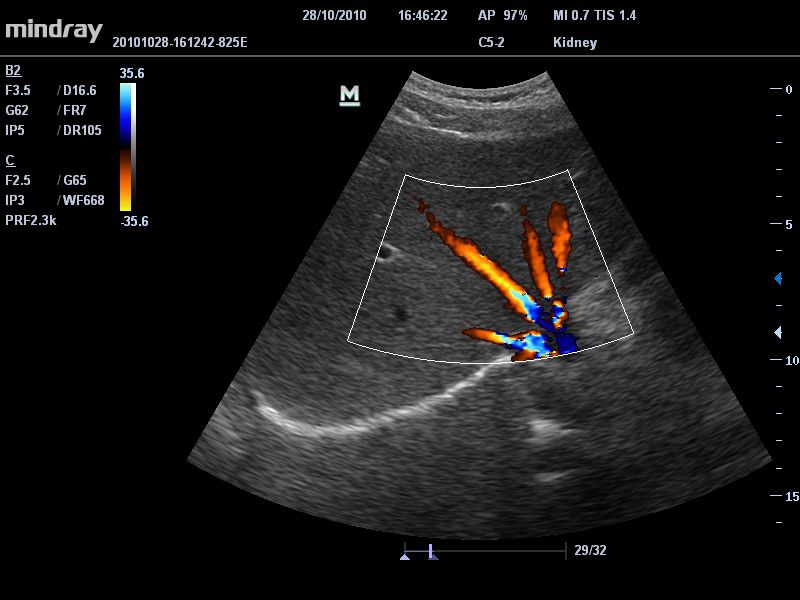

Цветовой допплер:

Да

• Режимы сканирования: B/M/CFM/PDI/Направленный PDI/PW, HPRF, Тканевая гармоника, М- и цветной М-режим.

• Микроконвексный датчик Mindray 6C2